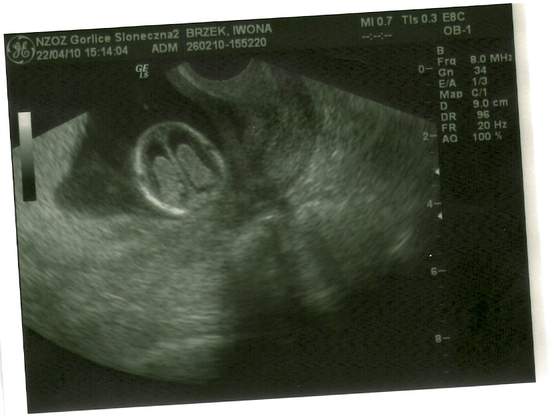

skanowanie0003.jpgskanowanie0004.jpgskanowanie0002.jpga to moja niunia:-)

no i oczywiscie wsio ok jest 2 raczki 2 noznki po 5 paluszkow:) 2 komory mozgowe serducho bije jest zoladek i pecherz moczowy czyli nerki pracuja NT-1.5 KOSC NOSOWA UWIDOCZNIONA:) NO I STRASZNIE LUBI ZAKLADAC NOGE NA NOGE...HMMM